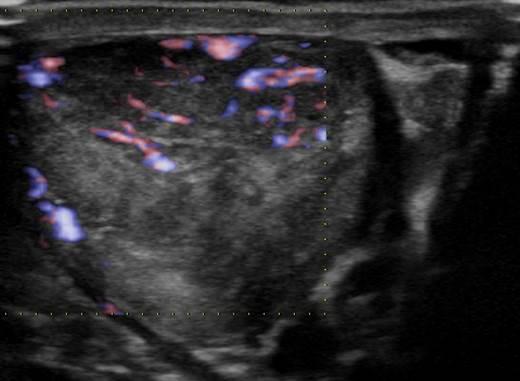

U tinh hoàn - Ảnh 4

U tinh hoàn

» Thông tin: Nam giới – 35 tuổi.

» Lâm sàng: Sưng tinh hoàn.

# U tinh bào (Seminoma).